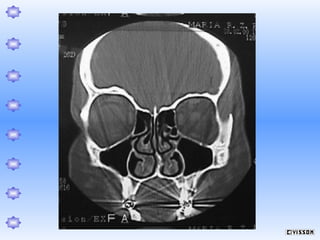

Espessamento mucoso a direita e

Cisto sub-mucoso à esquerda